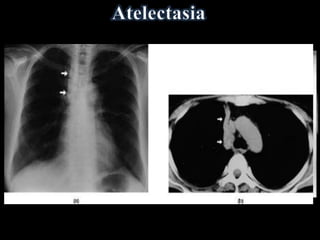

Redução do componente aéreo pulmonar com

perda volumétrica associada

(colapso parcial do pulmão).

Diretos

• Aproximação de vasos

e brônquios

• Deslocamento de

cisuras interlobares

Indiretos

• Elevação da cúpula

• Aproximação de

costelas

• Desvio do mediastino

• Deslocamento dos

hilos

• Hiperinsuflação do pulmão remanescente